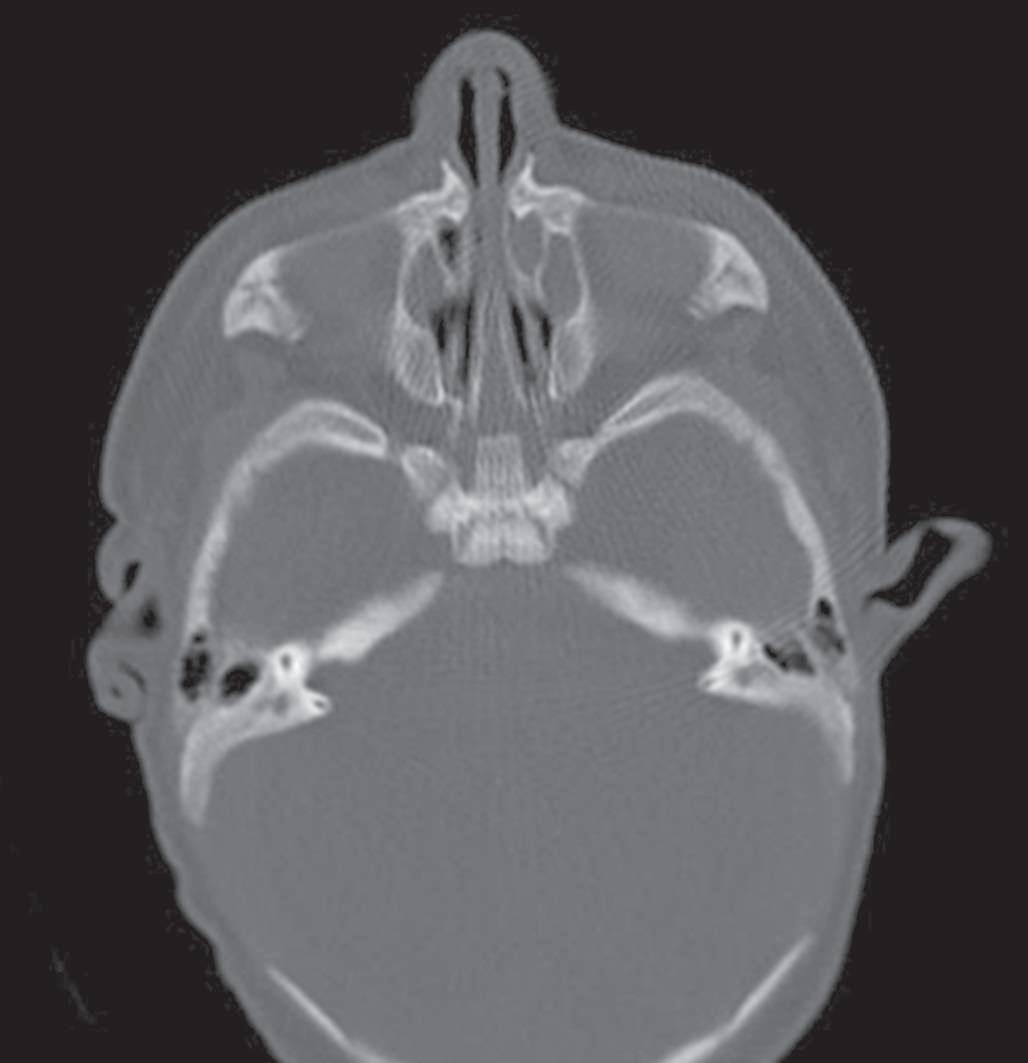

A tomografia computadorizada (TC) é o exame de escolha: valores abaixo de 11 mm são considerados sugestivos. Alguns autores mais rigorosos consideram o limite inferior de 8 mm (Fig. 1-1). A TC também avalia malformações associadas e estruturas como lâmina cribriforme e base do crânio.9 O diagnóstico diferencial deve incluir atresia de coanas, cistos, encefaloceles e tumores. A endoscopia nasal é útil para localização da obstrução.5,10

Além da correção esquelética, a ERM proporciona alargamento da base nasal, promovendo a redução da resistência ao fluxo aéreo e, consequentemente, aumento da ventilação nasal (Fig. 1-4).

9. Ao final da expansão, nova TC pode ser realizada para mensuração objetiva do ganho de espaço aéreo (Fig. 1-4), além da avaliação clínica (Fig. 1-8).

Apesar da eficácia da técnica de desgaste ósseo na abertura piriforme, seus potenciais riscos e complicações levaram ao aparecimento de outras opções terapêuticas. Vários estudos demonstraram que a atresia é maxilar, não se limitando ao piriforme, mas se estendendo por quase toda a cavidade óssea nasal.12,14 A expansão rápida da maxila, com dispositivo disjuntor e ancoragem esquelética por meio de miniparafusos, com sua fundamentação anatômica, biomecânica e funcional, é menos invasiva, proporciona uma expansão tridimensional eficaz ao longo de toda a fossa nasal, produzindo uma melhora funcional consistente nas vias aéreas superiores, que se mantém ao longo de todo o período de crescimento craniofacial (Fig. 1-9). Assim, a ERM credencia-se como técnica de escolha no tratamento da ECAP.15